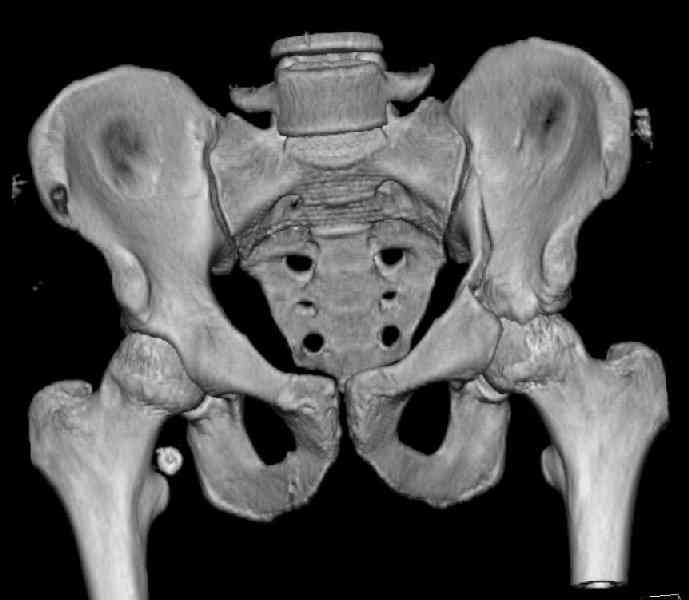

The last two images from the 3-D CT scan certainly makes the fracture look worse than the plan radiographs.

Might have to reconsider my suggestion to leave it alone at this stage.

Ilioinguinal approach would be the best to approach and clean out fracture with recon plate fixation as suggested by Dr. Venkatachalam.

The joint is non-concentric as the head appears to be either "following the caudal segment", or the dome component is displaced from the tethered head... or so it seems... and he's young... so, many fracture surgeons would recommend reduction and fixation.

So we must decide preoperatively which part is the displaced segment?

It's difficult to know from these few selected images which component of the injury (was before and now) should be deemed the "soon to be mobile"

segment. It's my best guess that it is the caudal portion and there exists a healing fracture line somewhere thru the posterior column...one image

suggests it. If true, its early healing/union should be disrupted, and the resultant fragment mobility then allows accurate reduction.

Such work is not always possible using a single exposure... it's not unreasonable to first access the healed zone and osteotomize it using one direct exposure, then turning the patient if necessary to use another opposite exposure to further mobilize the fracture, reduce, clamp, and fix it.